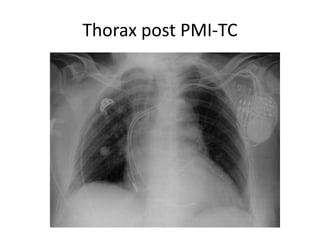

• Décision arbitraire d’implanter un PMI-TC

plutôt qu’un DAI-TC compte tenu de l’âge.

Thorax post PMI-TC